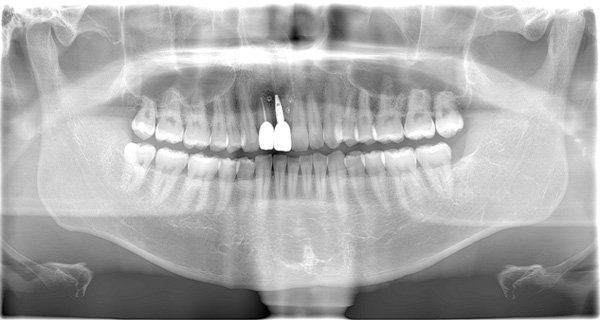

| 年代・性別 | 50代 男性 |

|---|---|

| 主訴 | 右下の歯が割れてしまったのでインプラントをして欲しい |

| 治療期間 | 約6ヶ月 |

| 費用 | 1,100,000円 |

| 治療内容 | インプラント、骨造成、結合組織移植、セラミック修復 |

| 治療に伴うリスク | インプラント周囲炎 セラミックの破折、脱離 |